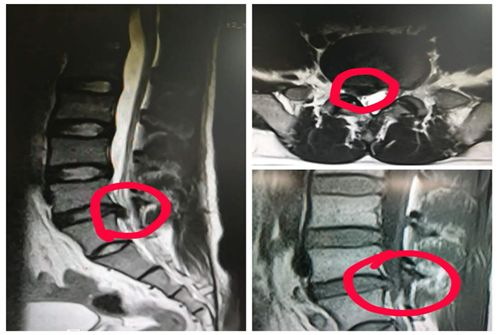

△影像学检查可见明显腰椎间盘突出